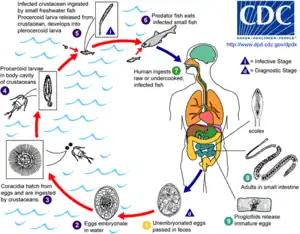

There are three main kinds of parasites: Clonorchis sinensis (a trematode/fluke), Anisakis (a nematode/roundworm) and Diphyllobothrium (a cestode/tapeworm). Infection by the fish tapeworm Diphyllobothrium latum is seen in countries where people eat raw or undercooked fish, such as some countries in Asia, Eastern Europe, Scandinavia, Africa, and North and South America.[71] Infection risk of anisakis is particularly higher in fishes which may live in a river such as salmon (shake) in Salmonidae, mackerel (saba). Such parasite infections can generally be avoided by boiling, burning, preserving in salt or vinegar, or freezing overnight. Even Japanese people never eat raw salmon or ikura (salmon roe), and even if they seem raw, these foods are not raw but are frozen overnight to prevent infections from parasites, particularly anisakis.

Below are some life cycles of fish parasites that can infect humans:

Life cycle of the parasitic Anisakis worm Life cycle of the fish tapeworm Diphyllobothrium latum

Life cycle of the fish tapeworm Diphyllobothrium latum Life cycle of the digenean Metagonimus, an intestinal fluke

Life cycle of the digenean Metagonimus, an intestinal fluke